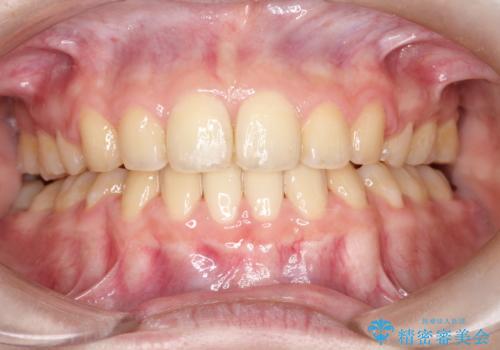

- 口元が出てるのが気になるとのことで来院されました。

歯のがたつきはあまりなかったのですが、口唇が閉じずらく、口元の突出感が確認できました。

上下左右の歯を1本ずつ抜歯して、そのスペースを利用して口元を引っ込める計画としました。